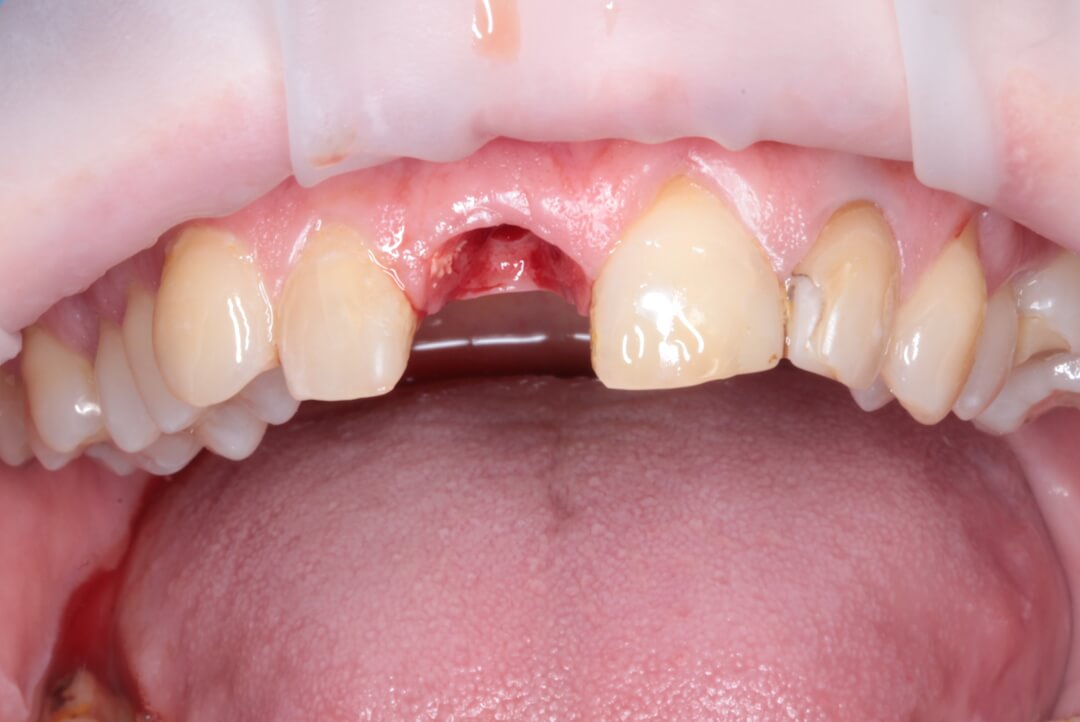

Рис. 2. Вид пациентки после всех проведенных манипуляций в первое посещение.

Рис. 3. Вид пациентки на 10 сутки (снятие швов).